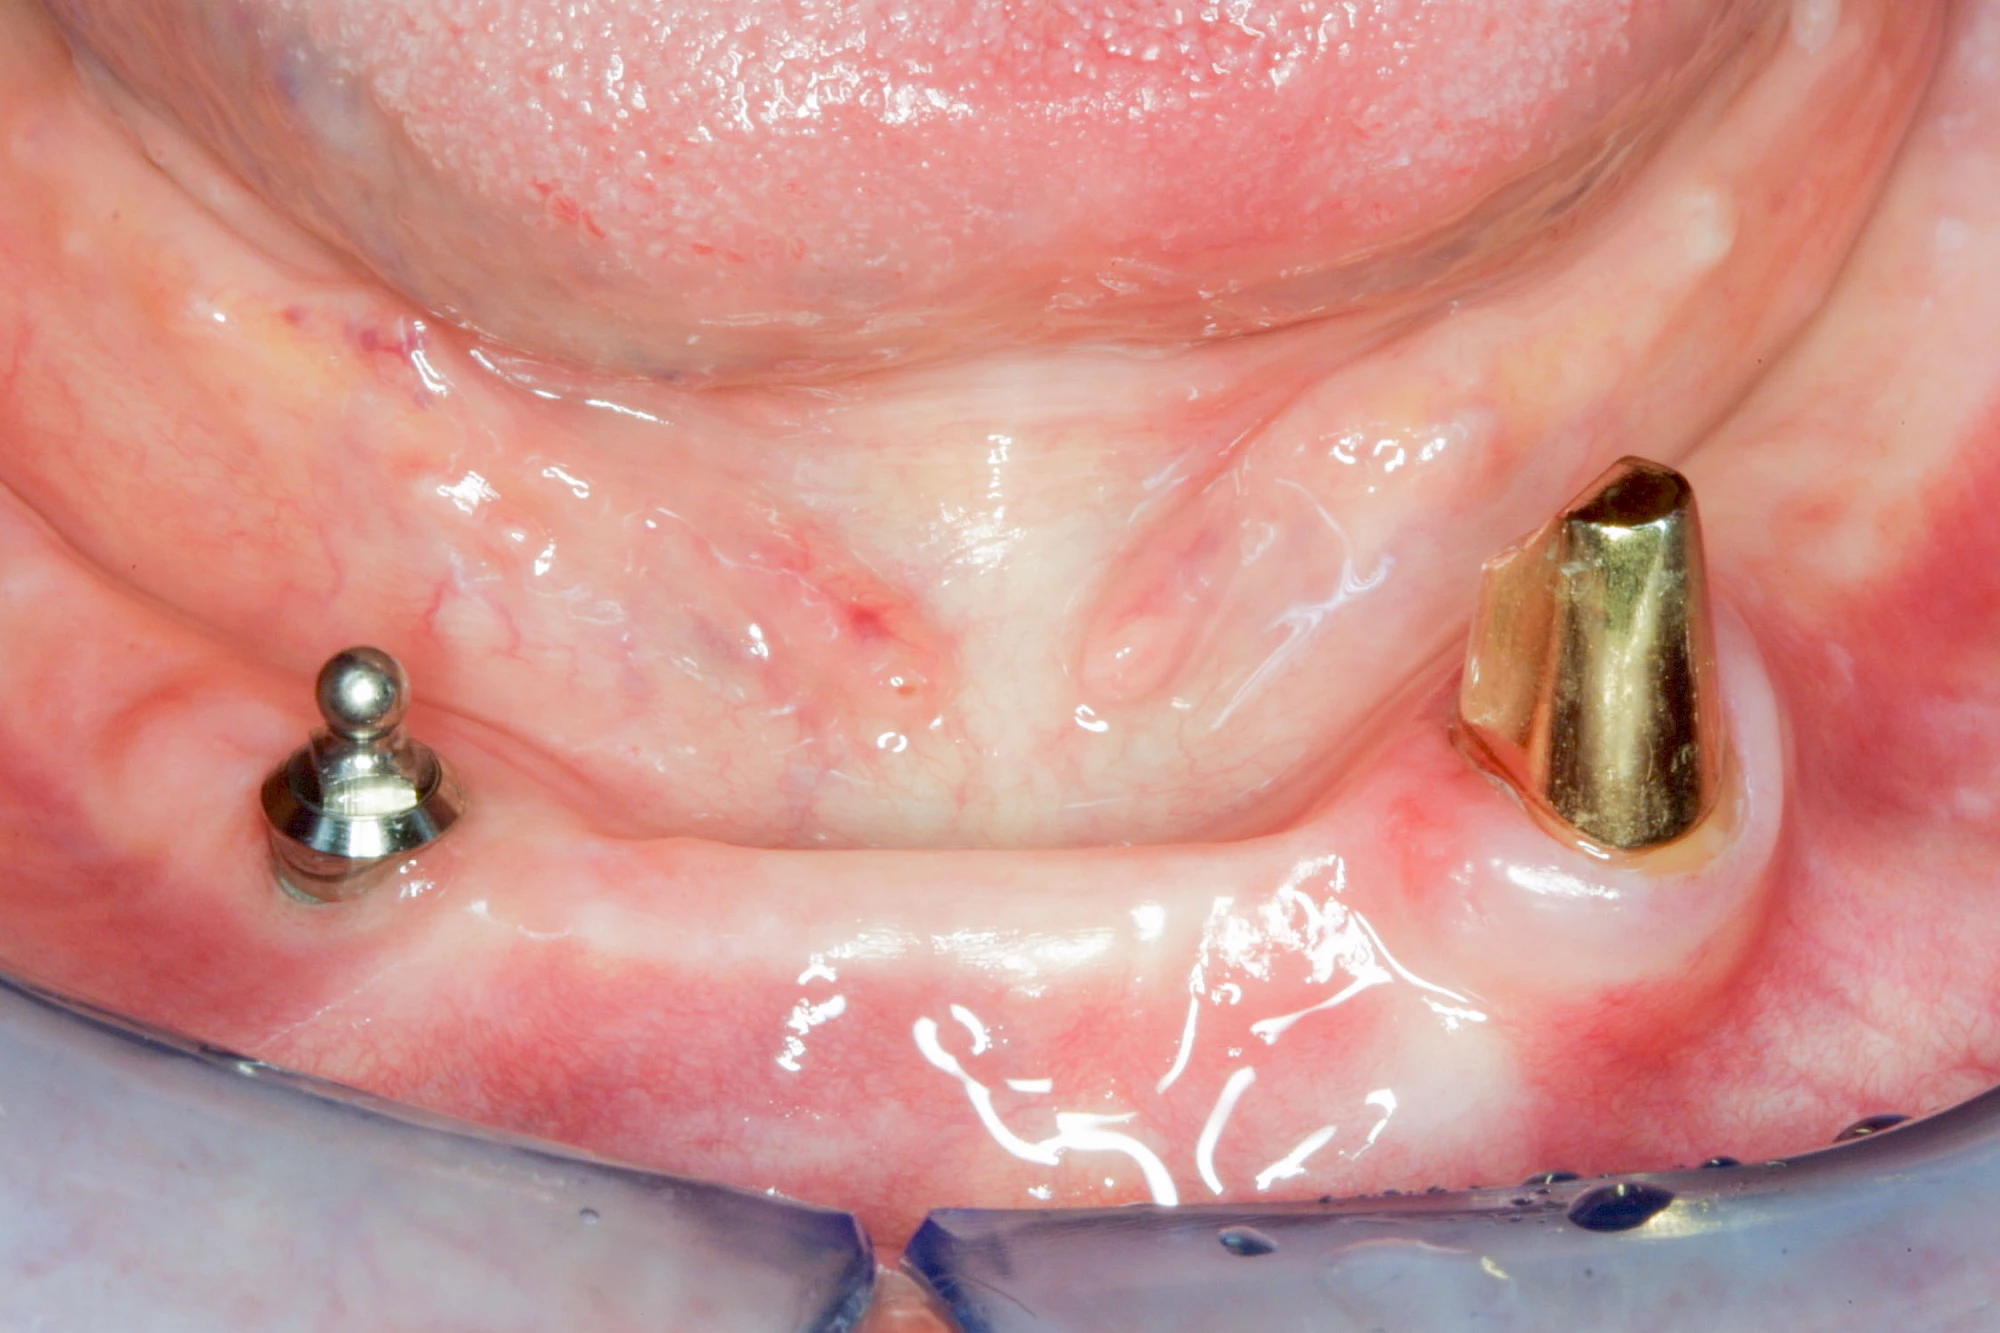

Implantate: Prothesen

Bei herausnehmbaren Prothesen werden Implantate eingesetzt, um den Halt und den Tragekomfort der Prothesen zu verbessern. Dazu kommen verschiedene Verbindungselemente zum Einsatz:

- Teleskope

- Kugelköpfe

- Tellerförmige Lokatoren

- Stege

- Magnete (selten)

Neben rein implantat-getragenen zahnärztlichen Versorgungen werden bei herausnehmbaren Prothesen Implantate auch in Sinne einer "strategischen Pfeilervermehrung" ergänzend zu eigenen Zähnen zur Verankerung eines Zahnersatzes genutzt.

Varianten zur Verankerung von abnehmbarem Zahnersatz auf Implantaten